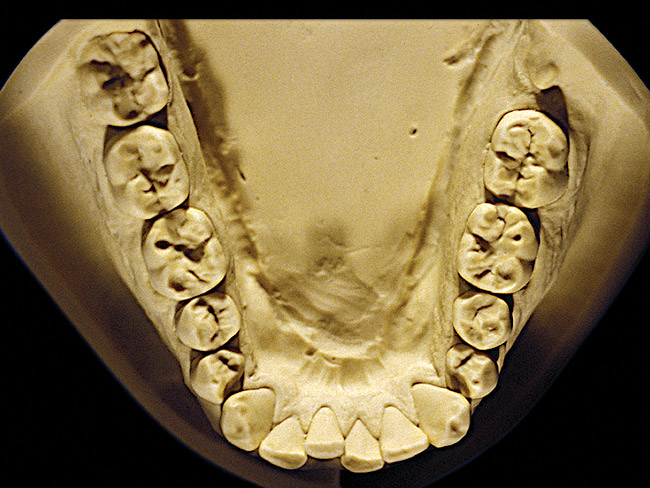

Figure 8  Moderate NCLTS from toothpaste, mandibular arch.

Figure 12  Advanced NCLTS from toothpaste, mandibular arch.